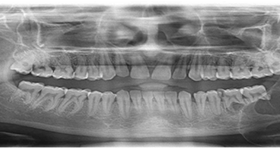

After a detailed planning phase which involves diagnostic impressions, radiographs and CT Scans, the dental implants will be placed into your jaw bone under local or general anesthesia. In certain conditions, we can go ahead and immediately restore these dental implants and you can walk out of the surgery with brand new teeth. In some cases, we will have to wait for a certain time period to ensure that the bone around the implant is healed before we replace the missing tooth or teeth.

All of the diagnostic imaging, including the radiographs and CT Scans, are also done at Amrapali Dental Clinic.